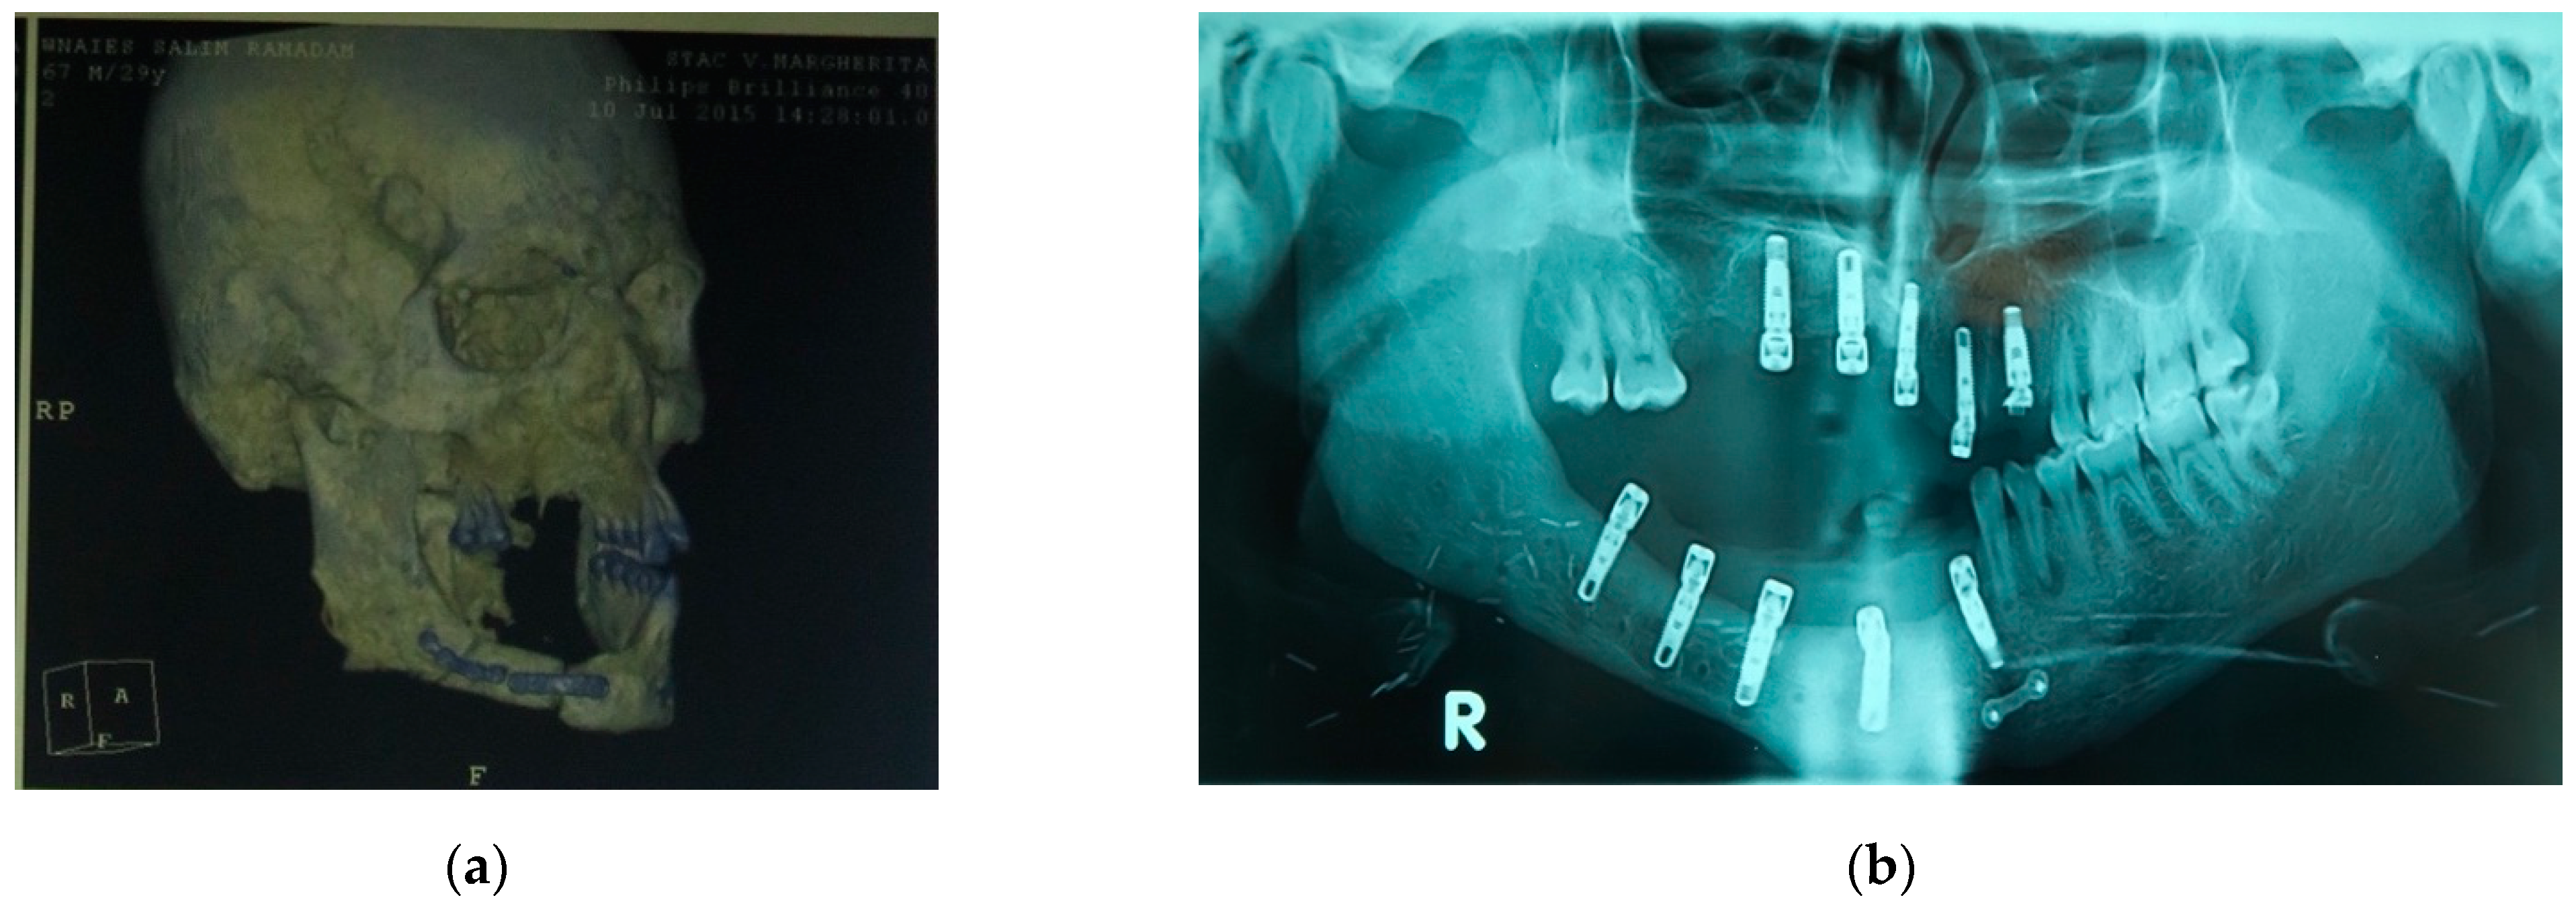

| 1 | 22/M | High-velocity injury | T4, Lower maxilla, Basal bone, Gingival tissue and Soft tissue | Emimandibulectomy dx | Free Fibula Flap | Fixed implant-supported prosthesis (n. 5 dental implants) |

| 3 | 29/M | High-velocity injury | T4, Upper maxilla, Basal bone, Gingival tissue and Soft tissue | Emimaxillectomy dx | Free Fibula Flap | Fixed implant-supported prosthesis (n. 6 dental implants) |

| 4 | 31/M | High-velocity injury | T4, Upper and Lower maxilla, alveolar bone, Gingival and Soft tissue | Alveolar Resection, I quad. + IV quad. | Free Iliac Crest Flap | Fixed implant-supported prosthesis (n. 10 dental implants) |